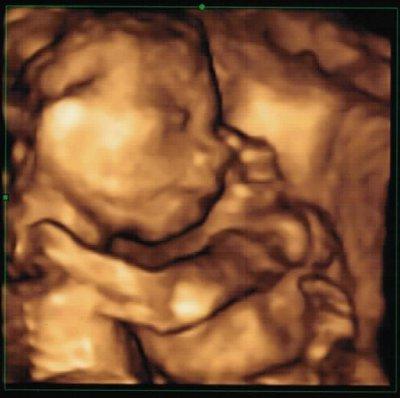

Hallo ihr Lieben, juhuu, heute beim 2. US haben wir auch ein Outing bekommen! Beim ersten Gucken meinte sie, zu 70 Prozent ein Mädchen. Nach dem zweiten Gucken zu 80 Prozent, dann meinte ich, okay ich frag in fünf Minuten noch mal. Da waren es dann schon 90 Prozent. Aber auf mehr wollte sich die FÄ nicht festnageln lassen. ^^ Reicht mir völlig, wird eh nicht alles rosa. Jippie!!! Ein Mädel!!! Und wenn es doch noch ein Junge wird, hat er auf jeden Fall Sinn für Humor ^^ Entwicklung alles super, ist sogar etwas größer als normal, aber da der Vater 1,98 cm groß ist, wissen wir, woher das kommt. *g* Die Ärztin war ganz lieb und hat einfach so mal auf 4 D umgeschaltet, hab ein voll schönes Bild bekommen. Ich bin heute echt wie auf Wolken, eine wunderschöne Tochter! Ich wünsch euch einen ganz tollen Abend und alles Gute für eure Bauchis!!! LG Snow

Bild zu Outing zu 90 Prozent :) - Forum für September - Mamis

Wooow, tolles Foto! Und herzlichen Glueckwunsch zur 90prozentigen Tochter... Wir haben einen 90prozentigen Sohn. ;-) Deine Suesse sieht aus, als halte sie ein Kuscheltier im Arm (ok, ich weiss, dass wir da drinnen keine Kuschelteddys haben), so goldig! Vielleicht schmust sie ja auch mit der Plazenta... Oder weisst du, was es ist? Geniess dieses unendlich schoene Gefuehl auf der Wolke Nummer 7. Ich bin letzten Donnerstag geflogen und wenn ich dein Posting so lese, dann heb ich gleich wieder mit ab. GLG Agi

Guten Morgen ihr Lieben, vielen Dank für die Glückwünsche :) Ich hab keine Ahnung, was sie im Arm hält, aber ich vermute mal, es wird ein Stück Plazenta sein. Herzlichen Glückwunsch zum Son @ Agi! Euch allen einen schönen Tag! Snow